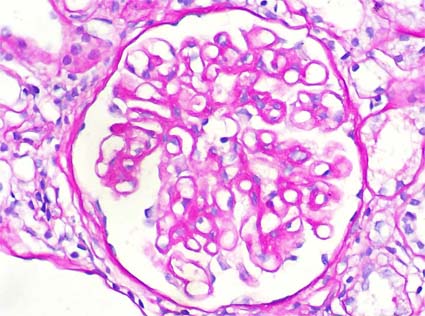

The mesangial matrix is formed by different types of collagen (III, IV, V and VI), microfibrillar proteins, glycoproteins, proteoglycans and other components (Venkatachalam MA, Kriz W. Anatomy (of the kidney). In Heptinstall's Pathology of the Kidney, Lippincott-Raven, Philadelphia, 1998, pp. 3-66) (Figure 4 and Figure 5).

Figure 5. The mesangial matrix also stains with the PAS, like the basal membranes, due to the affinity of PAS by type IV collagen (PAS, X300).